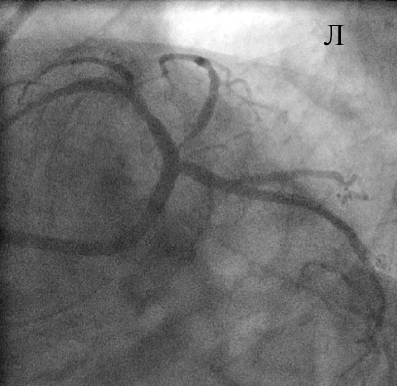

В устье ОВ с переходом на ее проксимальный сегмент был имплантирован стент XienceV (и), после чего выполнена постдилатация по методике «целующихся» баллонов (к). При контрольной КГ стентированные сегменты проходимы, достигнут хороший ангиографический результат (л).